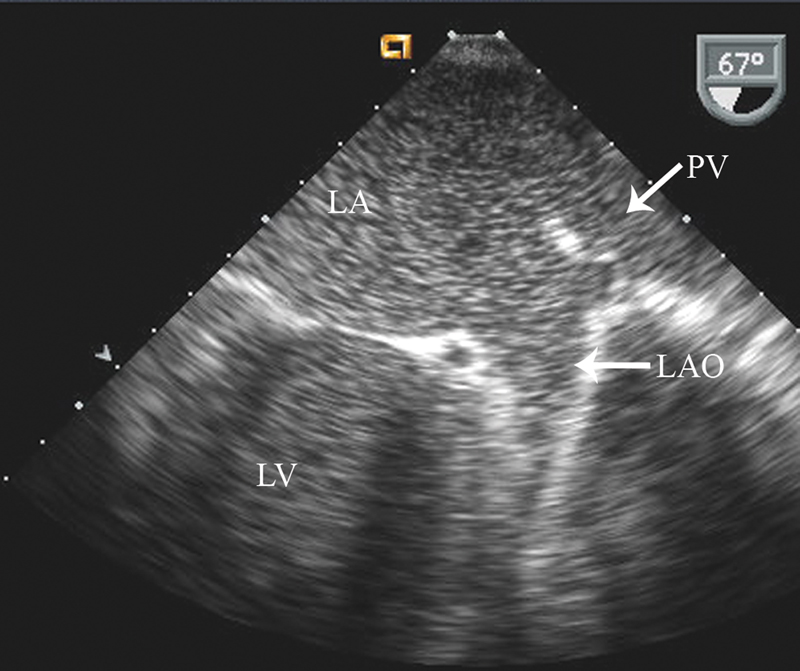

فحوصات تشخيصية لبعض امراض القلب والشرايين التاجية